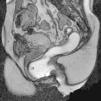

Cistocele. Es un prolapso de la vejiga por debajo del nivel de la sínfisis púbica, favorecido por un desgarro en la fascia pubocervical1,5 u otras estructuras de soporte4 (fig. 1). Un aumento de la presión abdominal y el descenso de la pared posterior de la vejiga pueden provocar que la uretra describa un movimiento rotatorio y quede en disposición horizontal por el mecanismo conocido como hipermovilidad uretral1,5.

Prolapsos uterino y vaginal. La cúpula vaginal y el útero, debilitados o diseccionados sus soportes ligamentosos y conectivos, ante la presión del contenido pélvico y abdominal descienden de su posición anatómica (fig. 1). En ocasiones lo hacen por el propio canal vaginal, evertiéndolo de dentro afuera. Los enteroceles y peritoneoceles también pueden empujar en su descenso al útero y la cúpula vaginal; en los casos más severos las paredes internas de la vagina se convierten en las paredes externas de un saco que emerge por el introito como una protuberancia blanda. Este saco contiene generalmente grasa peritoneal, asas del intestino delgado e incluso el propio útero descendido (fig. 2). Puesto que el prolapso vaginal y uterino se asocia frecuentemente al prolapso de otros órganos, la evaluación de la pelvis al completo mediante RM resulta particularmente importante1,5 (fig. 3).

Rectocele. Supone una proyección protuberante de la pared rectal, generalmente anterior, aunque también puede ser posterior o lateral. Suele producirse por encima del canal anal1,5, principalmente por defectos en el septo rectovaginal1. Cierta cantidad de heces puede quedar retenida en estos espacios, dificultando la defecación (figs. 1 y 3).